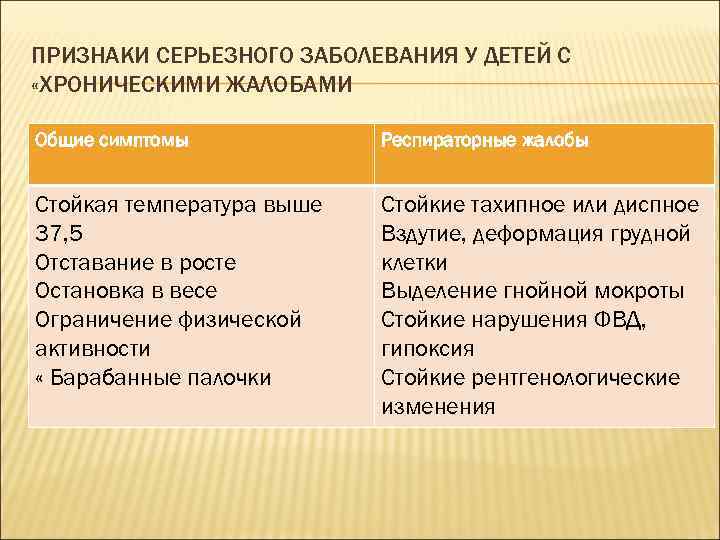

ПРИЗНАКИ СЕРЬЕЗНОГО ЗАБОЛЕВАНИЯ У ДЕТЕЙ С «ХРОНИЧЕСКИМИ ЖАЛОБАМИ Общие симптомы Респираторные жалобы Стойкая температура выше 37, 5 Отставание в росте Остановка в весе Ограничение физической активности « Барабанные палочки Стойкие тахипное или диспное Вздутие, деформация грудной клетки Выделение гнойной мокроты Стойкие нарушения ФВД, гипоксия Стойкие рентгенологические изменения